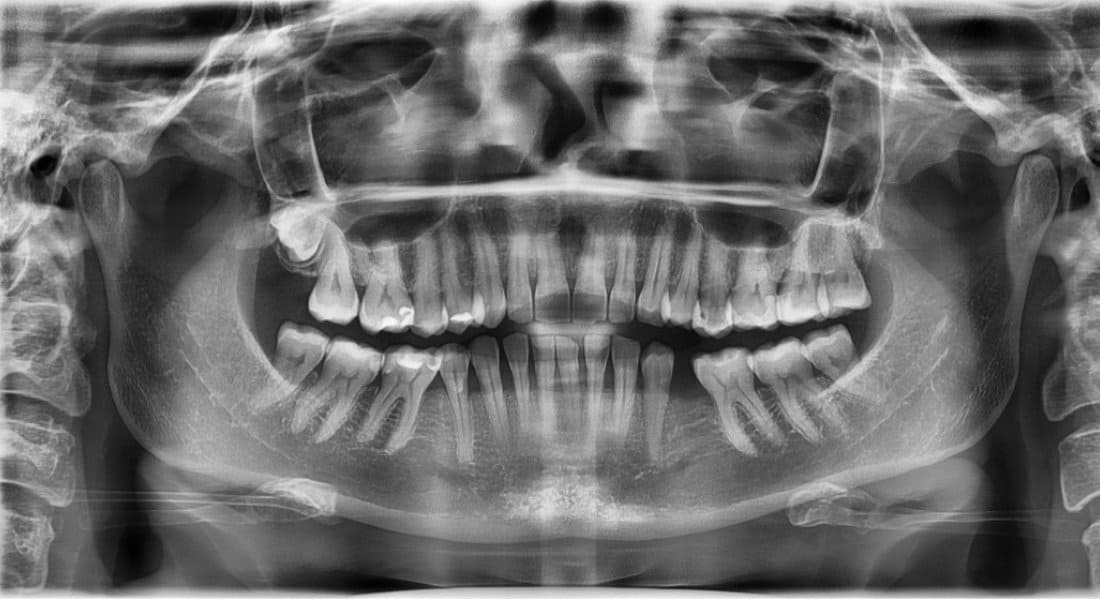

1) Опишите состояние костной структуры

2) Опишите состояние всех зубов

3) Описать прикус

4) Составить план лечения